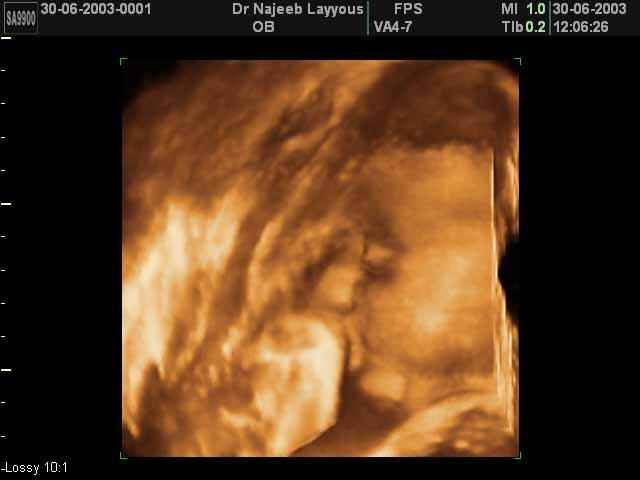

- 3D Fetal Profile Ultrasound Scan Photos

3D Fetal Profile Ultrasound Scan Photos | Dr N Layyous